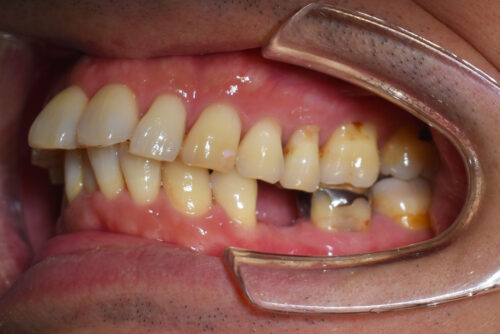

ワイヤー9か月後です。

本症例も

上顎左右臼歯部に

歯科矯正用アンカースクリュー(デュアル・トップオートスクリュー)を用い

下あごを オートローテーションさせ

また 上下の歯列全体を

後方へ移動させることで

歯を抜かなくても

口元の改善も行いました。

また、下顎の欠損部分は

全てスペースを閉じて

ご自身の歯で

かめるように

矯正治療を終えました。